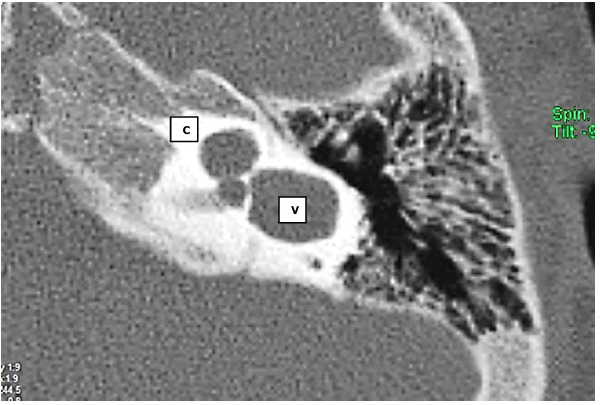

Paciente do sexo masculino, 2 anos, é encaminhado ao serviço de Otorrinolaringologia devido a atraso de fala e linguagem. Considerando a seguinte sequência de tomografia contrastada, é correto afirmar que:

A malformação em questão apresenta alterações semelhantes às encontradas na hipoplasia coclear tipo II.

Caso haja surdez bilateral de grau profundo, a reabilitação auditiva mais indicada, nesse caso, seria o implante de tronco.

Essa malformação é sempre acompanhada de perda auditiva de grau profundo.

Independentemente do exame audiométrico, esse paciente não é elegível para uso de Aparelho de Amplificação Sonora Individual (AASI).

Caso seja indicado implante coclear, o eletrodo de escolha deve ser o perimodiolar.